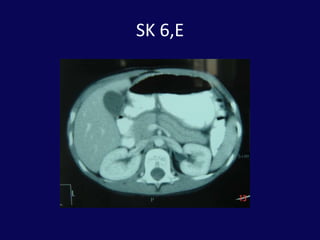

SK 6,E20 Gün önce bisikletten düşme dış merkezde taip batın distansiyonu gelişmesi üzerine İTF ne sevkFM: Distansiyon ve yaygın hassasiyet

BT: pankreas orta hatta laserasyon ve peripankreatik sıvı

SK 6,E